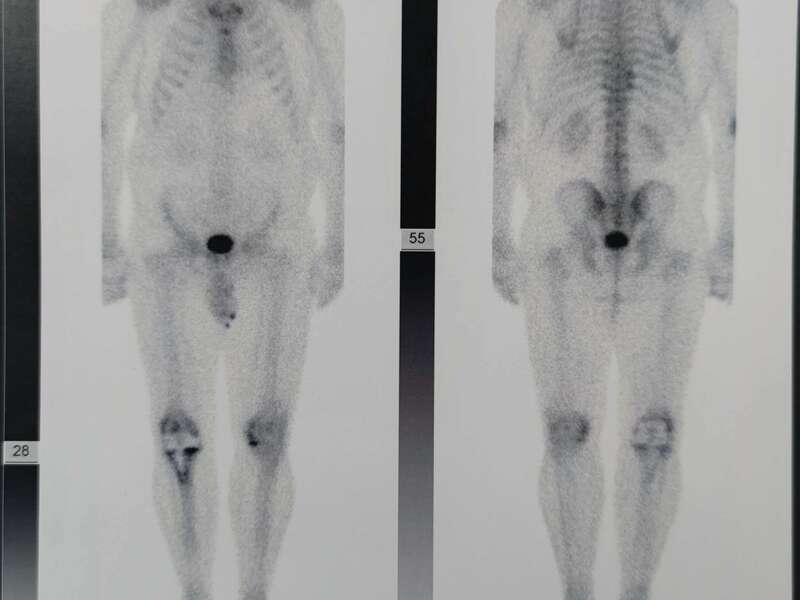

La scintigraphie osseuse est systématique. L’hyperfixation péri-prothétique est un argument en faveur du descellement d’une prothèse. Cet examen précise le site exact du descellement. Elle permet aussi de confirmer ou d’infirmer l’hypothèse infectieuse.